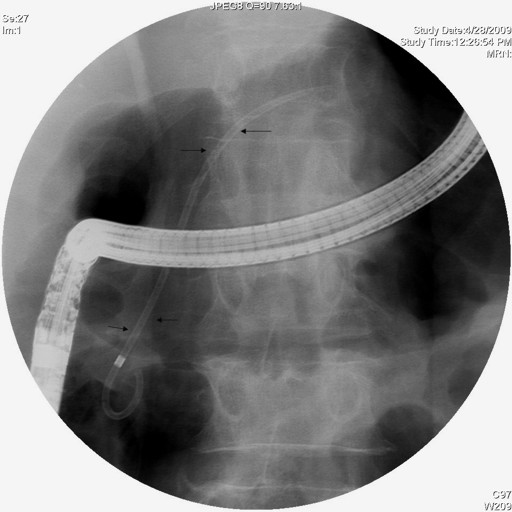

A 57-year-old man with a one year history of alcohol-induced chronic pancreatitis presented with a 1-month history of intermittent epigastric pain. He denied any associated nausea, vomiting, diarrhea, weight loss or other gastrointestinal symptoms. His past medical history was significant for hypertension, type 2 diabetes mellitus, dyslipidemia and chronic obstructive pulmonary disease. The abdomen was soft and non-tender. The liver and spleen were not felt, and no abdominal mass was appreciated. His physical examination was otherwise unremarkable. Laboratory evaluation revealed serum amylase of 356 U/L (reference range: 30-111 U/L) and a lipase of 679 U/L (reference range: 46-218 U/L). Complete blood counts, liver chemistries, carbohydrate antigen 19-9, and alpha-feto protein levels were all normal. Pancreas protocol CT scan of the abdomen revealed a 8x5 cm cystic fluid collection in the left liver lobe, an L-shaped subcapsular fluid collection inferior to right hepatic lobe 10x9 cm in size and a 2.4 cm complex fluid accumulation that involved the head and the superior aspect of the body of pancreas (Figure 1). CT guided diagnostic aspiration of the hepatic cystic lesion drained 100 mL of straw-colored fluid which showed no organisms on gram stain and was sterile on bacterial and fungal cultures. Cytological examination of the fluid did not reveal any malignant cells. The amylase level in this fluid was greater than 51,065 U/L which confirmed the diagnosis of intrahepatic pancreatic pseudocyst extension. At the time of CT guided aspiration, the pseudocyst was treated with percutaneous drainage with the placement of an 8F pig-tail catheter. The intrahepatic pancreatic pseudocyst extension failed to resolve even after 4 weeks of the pig-tail catheter placement (Figure 2). At this point, an ERCP was performed which revealed a normal cholangiogram. Pancreatography revealed a normal-appearing main pancreatic duct to the region of the pancreatic neck, and a ductal stenosis 12 mm in length was identified beginning at the pancreatic body near the neck. The main pancreatic duct and pancreatic duct branches were dilated upstream of the stenosis to about 7 mm (Figure 3). After performing an 8 mm ventral pancreatic sphincterotomy; the stricture was dilated with a 6 mm biliary dilating balloon and a 7F, 10 cm long pancreatic stent was inserted to the tail (Figure 4). Brush cytology and intraductal biopsy specimens were obtained from the stricture and revealed fibrosis and changes of chronic pancreatitis; they were negative for malignancy. EUS examination revealed a pancreatic head cystic lesion extending into the left hepatic lobe (Figure 5ab); fluid examination revealed an amylase of 54,450 U/L and the cytology was negative for malignancy. A follow-up pancreas protocol CT of the abdomen 6 weeks later revealed complete resolution of the pancreatic head fluid accumulation and the intrahepatic pancreatic pseudocyst and decrease in size of the L-shaped subcapsular fluid collection to 2x4 cm (Figure 6). Percutaneous drainage of the remaining L-shaped subcapsular fluid collection was discussed with the patient but he refused any percutaneous or surgical drainage. A follow-up pancreatogram revealed marked improvement in the pancreatic duct stricture. He remains asymptomatic after 9 months of follow-up.

Figure 4. ERCP showing the 7F, 10 cm long pancreatic stent traversing the main duct stricture extending to the tail. |